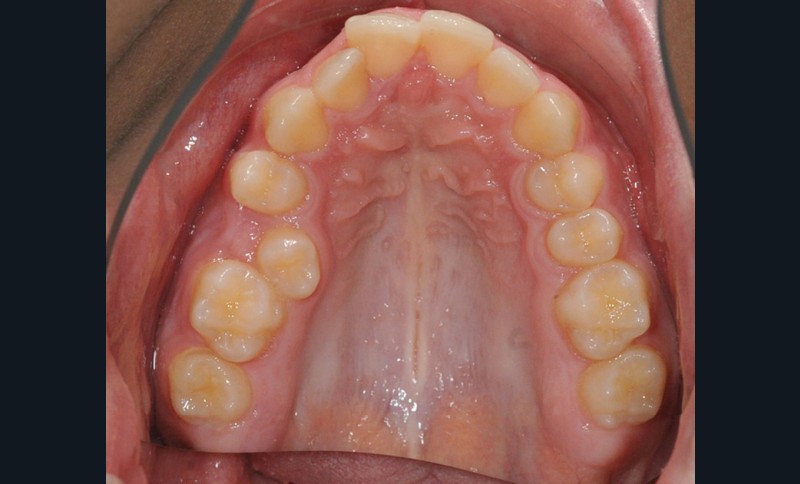

C’est à ces questions que nous permettront de répondre les deux premiers conférenciers, parodontologistes : le Dr Béatrice Straub nous présentera le renfort parodontal minéralisé, technique qu’elle a développée et pratique depuis de nombreuses années, pour éviter les préjudices des mouvements orthodontiques à risque, notamment lors des décompensations préchirurgicales (fig. 1a-d) ; le Pr Anton Sculean abordera le thème des greffes, avec leurs indications, les différentes techniques à privilégier et illustrera ses propos par de nombreux cas cliniques aux résultats esthétiques impressionnants.